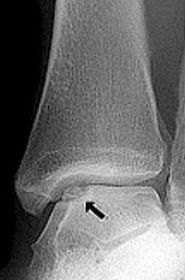

| What disease is this? What does the arrow indicate? | Rheumatoid arthritis. Arrow = Bone erosion secondary to inflammation of retrocalcaneal bursa. |

| What type of fracture is this? | Avulsion fracture |